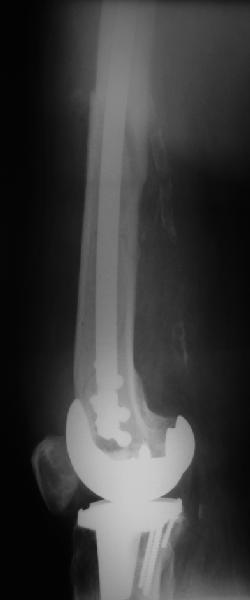

Представляю вам один из наших недавних случаев выполнения малоинвазивного остеосинтеза бедренной кости обычной пластиной 95 градусов. Длина восстановлена с помощью дистрактора (по сути это основная и б(о)льшая часть репозиции). Произведено два небольших доступа, проведена спица направитель. Рентген-контроль для подтверждения достаточной длины/оси (ЭОП использовался в другой операционной). Создание туннеля обратной стороной фиксатора. Поворот фиксатора, введение клинка по спице. Фиксация проксимального и дистального концов пластины.

Получилось очень симпатично, поздравляю и восхищаюсь мастерством.

Хотя закрытый остеосинтез блокированным гвоздем выглядит технически проще, особенно при диафизарных переломах. Не говоря о биомеханических преимуществах внутрикостного имплантата, еще меньшей инвазивности, возможности динамизации при проблемах со сращением... Стоимость гвоздей и пластин сопоставимая, на рынке есть масса отечественных предложений.